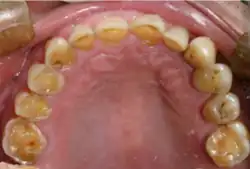

- usure des dents, parfois de manière importante, pouvant aller jusqu'à la nécrose ;

- le polissage de l'émail des dents afin de recréer un rééquilibrage correct de la mâchoire, pratique peu répandue car le bruxisme a pour conséquence l'usure importante de la face occlusale des dents si bien que l'émail a pratiquement disparu ;